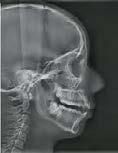

Figura 1. Estudios de inicio. A) Radiografía lateral de cráneo. B), C) y D), Fotografías extraorales (frente, frente con sonrisa y perfil). E), F), G), H), e I. Fotografías

intraorales (lateral derecha, frontal, lateral izquierda, oclusal superior, oclusal inferior).

Con los estudios realizados se confirmó clase III dental, depresión del tercio medio en la cara, observándose una discrepancia en el tamaño del maxilar contra la mandíbula y ausencia del OD 63, radiográficamente el OD 23 aún sin erupcionar (Figura 1).